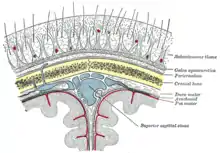

Layers

Most bones of the calvaria consist of internal and external tables or layers of compact bone, separated by diploë. The diploë is cancellous bone containing red bone marrow during life, through which run canals formed by diploic veins. The diploë in a dried calvaria is not red because the protein was removed during preparation of the cranium. The internal table of bone is thinner than the external table, and in some areas there is only a thin plate of compact bone with no diploë.[2] Calvarial bones are supplied by endosteal and periosteal sheaths which are innervated by the nociceptors, sensory, sympathetic, and parasympathetic nerves. Horizontal section of the mouse pups showed that the density of nerve fibers was highest in the region of forehead, temples, and the back of head which crossing the frontal, parietal, and interparietal bones. In the calvarial innervation in the adult mouse, CGRP-labeled fibers and peripherin were seen in the sutures, emissary canals, and bone marrow but not in diploe. Nerve fibers passing through the emissary canals and cavity of bone marrow provided the branches of periosteal and dural nerves whereas fibers from the sutures gave out to the dural nerves.[3]